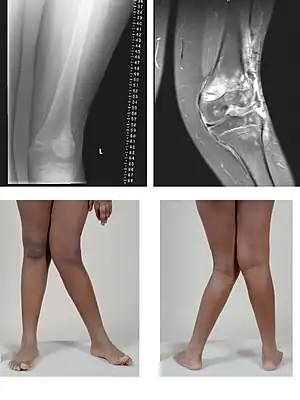

| Valgus deformity of the knee (genu valgum), seen in MRI and photograph | |

A valgus deformity is a condition in which the bone segment distal to a joint is angled outward, that is, angled laterally, away from the body's midline.[1] The opposite deformation, where the twist or angulation is directed medially, toward the center of the body, is called varus. Common causes of valgus knee (genu valgum or "knock-knee") in adults include arthritis of the knee and traumatic injuries.

- Knee: genu valgum (from Latin genu = knee) – the tibia is turned outward in relation to the femur, resulting in a knock-kneed appearance.

Rheumatoid knee commonly presents as valgus knee. Osteoarthritis knee may also sometimes present with valgus deformity though varus deformity is common. Total knee arthroplasty (TKA) to correct valgus deformity is surgically difficult and requires specialized implants called constrained condylar knees.